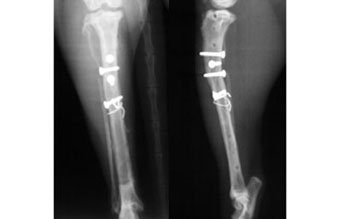

体重4kgの猫の脛骨骨幹部粉砕骨折。

ラグスクリューと細ピンによる骨片安定化とプレート固定術により整復固定しました。

写真上段: 手術前

骨幹部が縦に割れて多数の骨片に分かれています。

写真中段: 手術直後

骨片をラグスクリューと細ピンによりひとつにまとめてから、ほぼ全長にプレートをかけて固定しています。

写真下段: プレート除去後

ラグスクリューなどはそのままとなります。